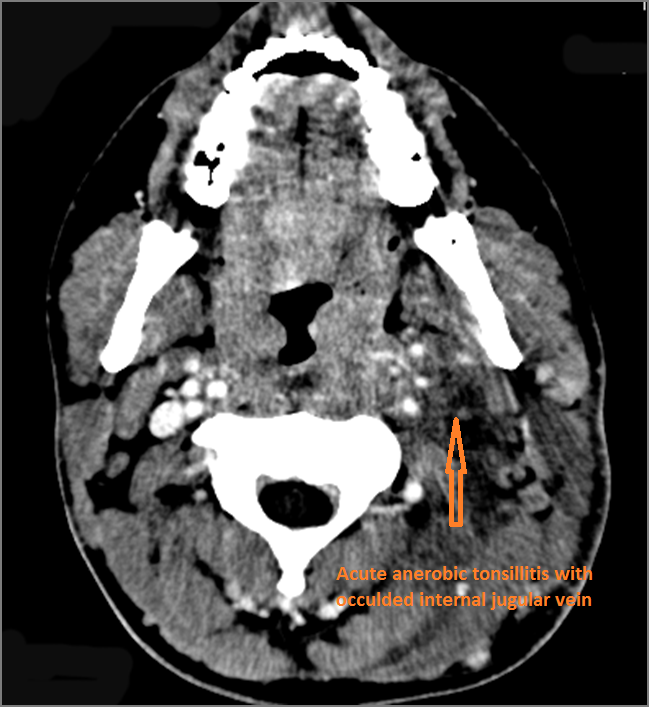

1-year old with fever, difficulties feeding and possible retropharyngeal abscess.Exam

Contrast-enhanced CT of the maxillofacial region and neck and related anatomy with images obtained in the balanced or venous vascular phase to ensure optimal visualization of both arterial and venous structures as well as possible reactive changes around infected collections. 0.5-3.0 mm thick sections were obtained in the axial plane and reformatted 3D and/or in the coronal and sagittal planes and viewed inter actively in 3 dimensions at the computer work station.